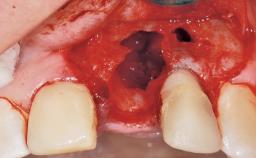

A 30-year-old female patient had lost tooth 21 and was referred to our clinic for consultation and treatment. Due to advanced apical infection, tooth 21 had been extracted two months earlier at another clinic and an acrylic-resin tooth had been bonded to the adjacent teeth. The patient desired implant treatment to avoid any damage to the adjacent natural teeth. While the patient had no history of any systemic disorder, she was a heavy smoker and exhibited medium to advanced periodontitis in the entire jaw. After the initial treatment to achieve a pocket probing depth of less than 4 mm and no bleeding on probing, a decrease in the height of the papillae mesial and distal to the extraction site and overall gingival recession were observed.

| Soft Tissue Grafting | Simultaneous |